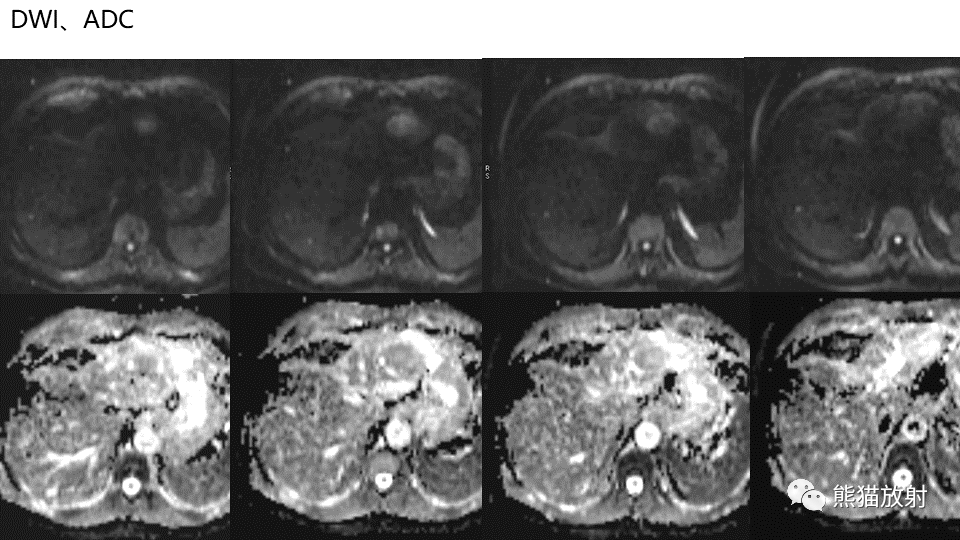

【PPT】肝内胆管细胞癌 VS 肝脓肿